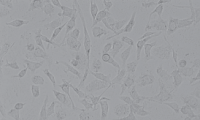

细胞名称: BIU-87人膀胱癌细胞

细胞形态: 上皮细胞样

生长特性: 贴壁生长

BIU-87建系于1989年,该细胞系来源于人膀胱乳头状移行上皮癌,通常采用5×108细胞0.2mL接种裸鼠皮下,呈进行性肿瘤生长,肿瘤结节病检与原标本癌组织相似。22代细胞群体倍增时间为34小时。细胞能在软琼脂上生长,克隆形成率23%。BIU-87细胞系对ConA,WGA,PSL均有凝集反应。